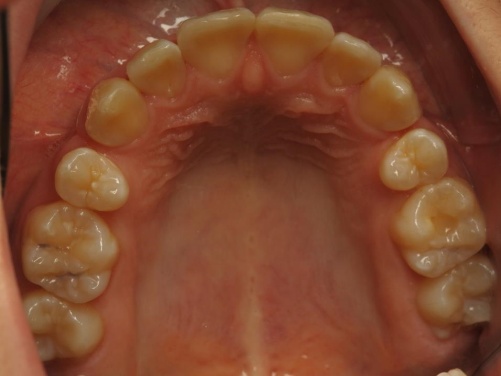

3 - Vues occlusales avec espaces d’extraction

Les vues occlusales montrent les espaces d’extraction des prémolaires au début du traitement, puis leur fermeture progressive. Les dents antérieures encombrées ont été alignées grâce au recul des canines dans ces espaces, sans déplacement des incisives centrales. La face vestibulaire de ces dernières est restée inchangée, préservant ainsi les rapports entre la lèvre supérieure et les incisives avant et après traitement. Les extractions n’ont donc pas entraîné de recul global, mais simplement créé la place nécessaire.